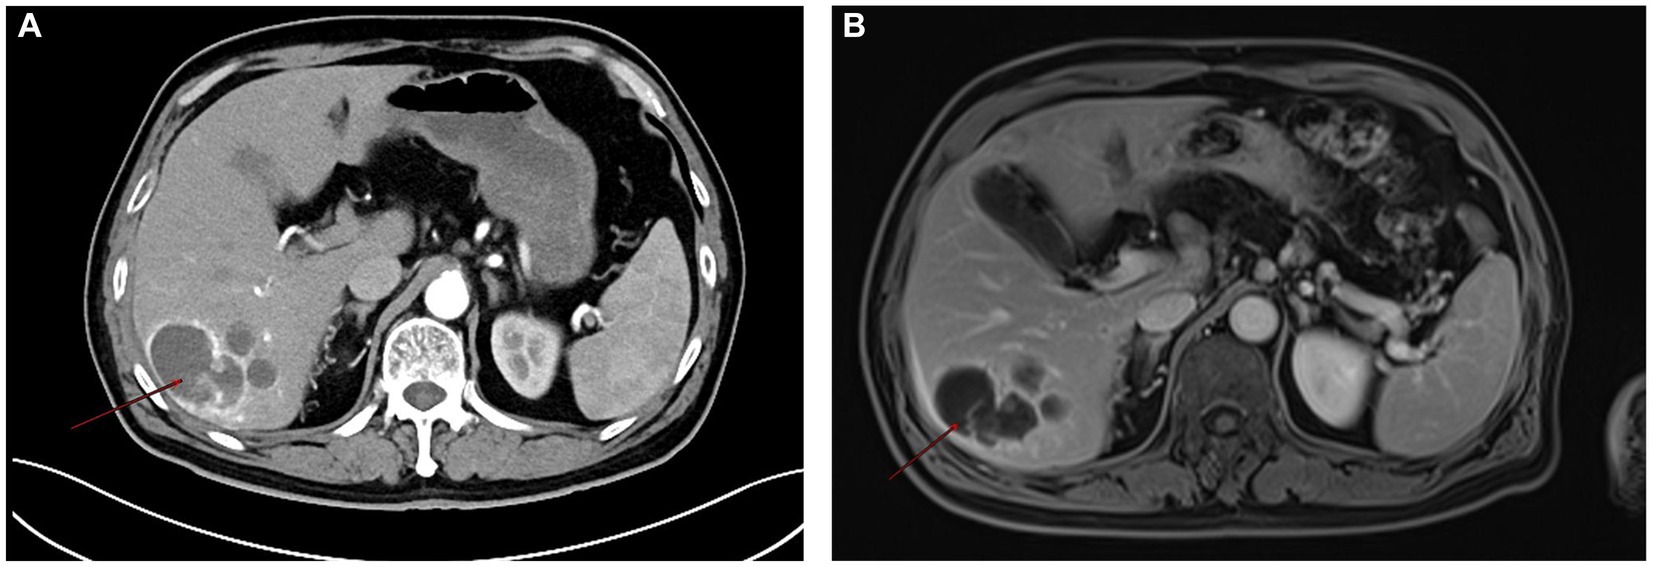

Primary hepatic malignant mesothelioma (PHMM) is an uncommon and aggressive neoplasm with vague clinical and radiological features, posing challenges for preoperative diagnosis. In our case, a lobulated hepatic mass demonstrated a serpiginous peripheral enhancement pattern on contrast-enhanced CT and MRI. This uncommon imaging manifestation has been sporadically documented in previous reports. By consolidating these findings, our report emphasizes serpiginous peripheral enhancement as a potential diagnostic clue for PHMM. Recognition of this pattern may aid earlier detection, improve differential diagnosis, and guide timely surgical decision-making in affected patients.